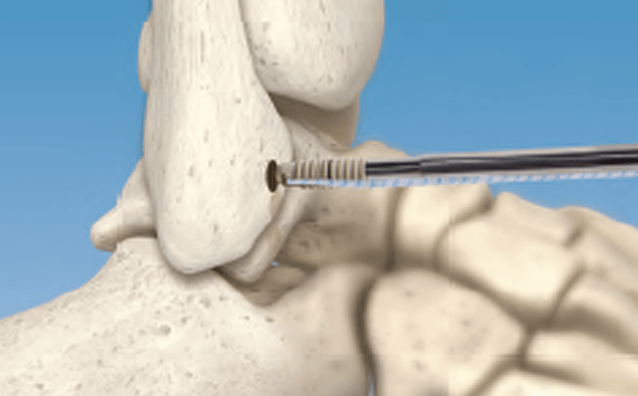

Arthroscopic Talus OCD Repair with CartiMax® Viable Cartilage Allograft - Dustin D. Constant, DPM